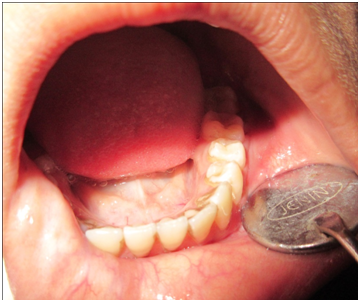

An 18year old female patient reported to the department of Oral Pathology, Dr. R Ahmed Dental College & Hospital, Kolkata with a complaint of swelling since 2years on the lower left jaw (Figure 1). The swelling was slow growing and painless. It was visible on the left side of the mandible and extended from left lower canine to left lower 2nd molar tooth (Figure 2). It was found as bony hard in consistency and non tender on palpation. Intra-oral examination revealed a dome shaped swelling measured approximately 4cmx3cm present on buccal vestibule of left mandible without any ulceration on overlying mucosa. The teeth involved were mobile and tender to pressure and percussion. Panoromic X ray revealed a distinct radio-lucency of approximately 5cmx3cm in size while scattered radio opacity was observed throughout the lesion (Figure 3). From this, the lesion could be provisionally diagnosed as fibro-osseous lesion/ameloblastoma. A biopsy was performed with local anesthesia and microscopic examination revealed fibro cellular stroma with multiple round oval hematoxyphilic calcified matrix similar to cementum/osteoid like material. There were no atypia or mitotic figures (Figure 4). These observations were consistent with cement ossifying fibroma. The management consisted of conservative surgical excision by curettage enucleation under local anesthesia raising mucoperiosteal flap. Post operative follow up was advised and after 6 month follow up the patient not reported any discomfort and panoromic X ray confirmed good bone regeneration in the operative zone.

Figure 2 Clinical appearance of patient at intra oral examination.